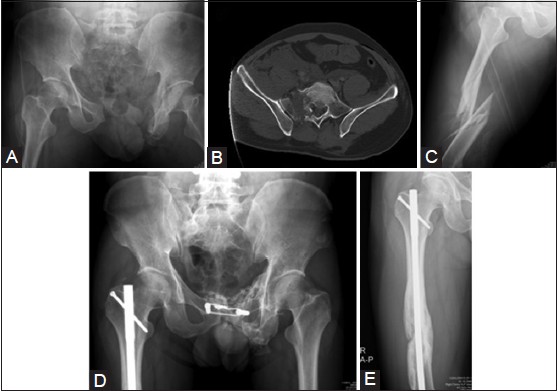

Background: Both pelvic fractures and femoral shaft fractures are caused by high-energy injuries. When unstable pelvic fractures and femoral shaft fractures occur concomitantly, the optimal treatment method is controversial. The aim of this study was to establish a reasonable principle for treating such complicated injuries.

Methods: Forty patients sustaining unstable pelvic fractures and concomitant femoral shaft fractures were treated in a 7-year period. The initial management of the fractures was started at the emergency service according to the Advanced Trauma Life Support protocol. Unstable pelvic fractures were wrapped by cloth sheets and femoral shaft fractures were immobilized with a splint. Angiography was performed on patients with unstable hemodynamic status. The definitive treatment for combined fractures was performed after stabilizing the hemodynamics. Closed nailing was used for femoral shaft fractures, and pelvic fractures were treated with various techniques.

Results: The mortality rate was 12.5% (5/40) during admission. Thirty-three patients were followed up for an average of 32 months (range, 12-76 months). There were 33 cases of unstable pelvic fractures and 36 instances of femoral shaft fractures. The union rate for pelvic fractures was 100% (33/33), while femoral shaft fractures had a 94.4% (34/36) union rate. The average healing time was 3.3 months (range, 1.6-8.1 months) and 4.1 months (range, 2.5-18.2 months) for pelvic and femoral shaft fractures, respectively. After fracture, 34 hips (94%) achieved a satisfactory result in the Harris hip score and 30 knees (83%) achieved a satisfactory result in the Mize knee score.

Conclusions: Stabilization of the hemodynamics in patients with combined fractures should be the first aim. Angiography to stop arterial bleeding in the pelvis is often life-saving. The definitive treatment for combined fractures, such as pelvic fractures and femoral shaft fractures, should wait until hemodynamics is stabilized.